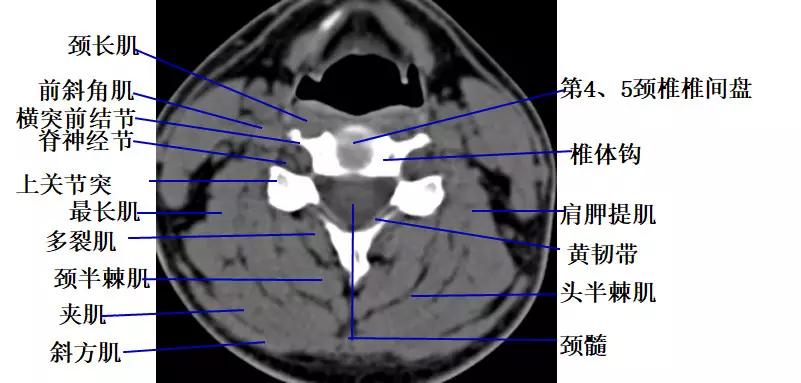

颈段横断面解剖及影像:

1. 经寰枕关节的横断层面(CT)

2.经环枢关节的横断层面(CT)

3.经颈椎椎弓根的横断层面(CT)

4.经颈椎椎体下部的横断层面(CT)

5.经颈椎椎间盘的横断层面(CT)